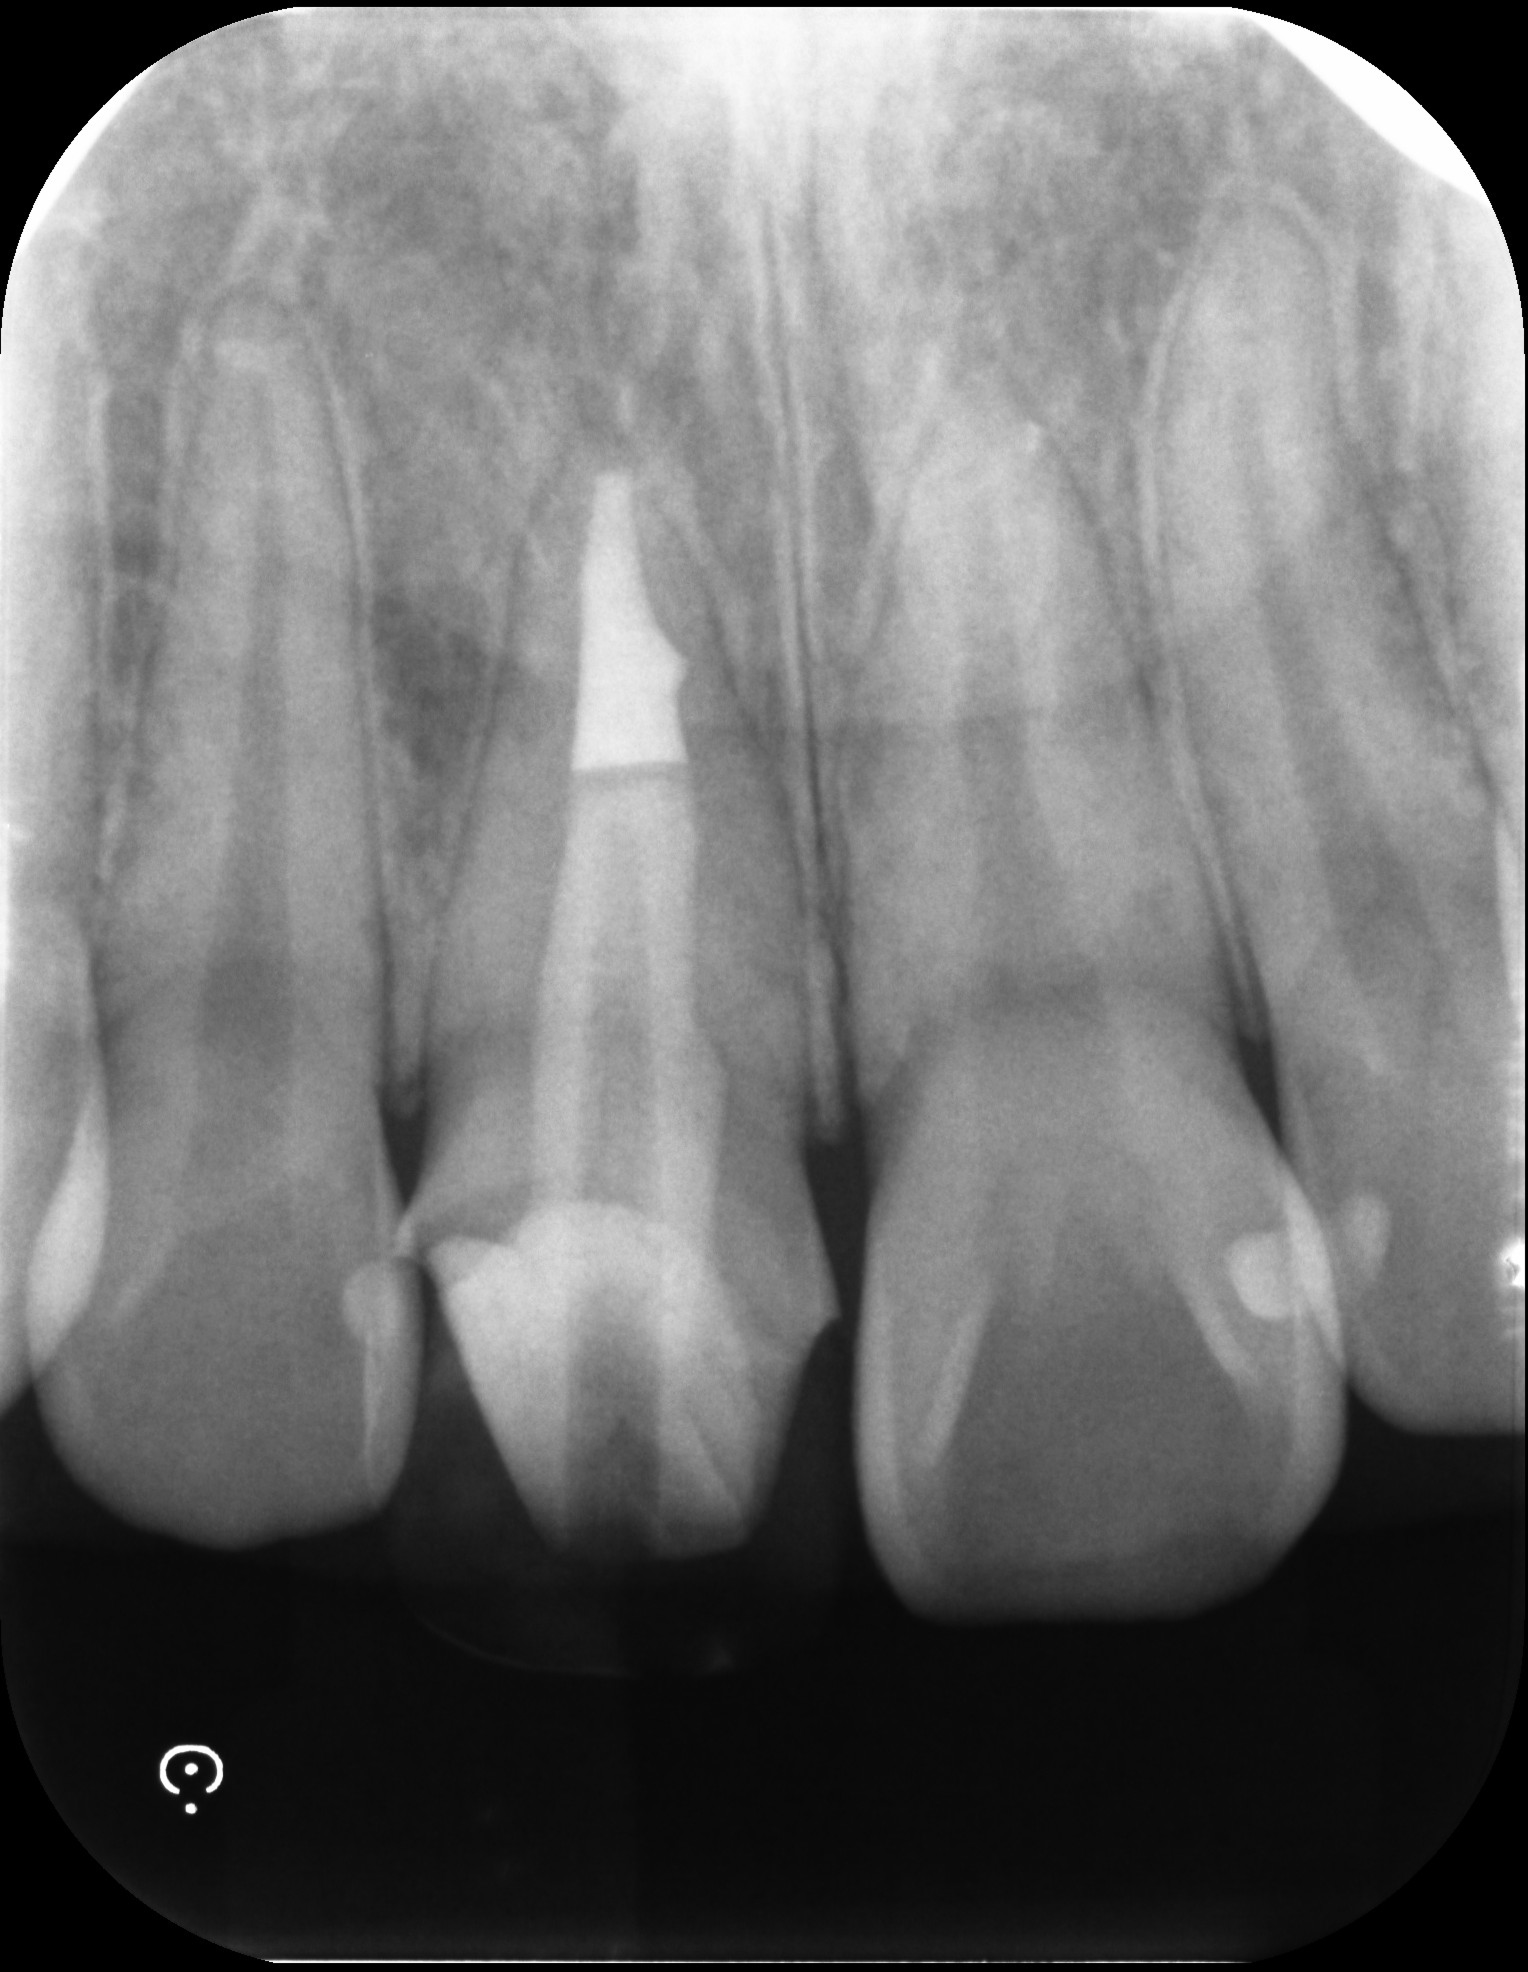

前歯の再根管治療を行った症例

タップで写真の拡大ができます。

Before

After

主訴

前歯を綺麗にしたい

治療内容

再根管治療(前歯)、ファイバーポストコア

治療期間

1ヶ月

治療費用

770,000

治療の

リスク

処置中に歯肉縁下におよぶ重度のう蝕や破折を認めた場合、治療を中断する可能性があります。術後も症状が残る場合は追加の処置が必要になる可能性があります。